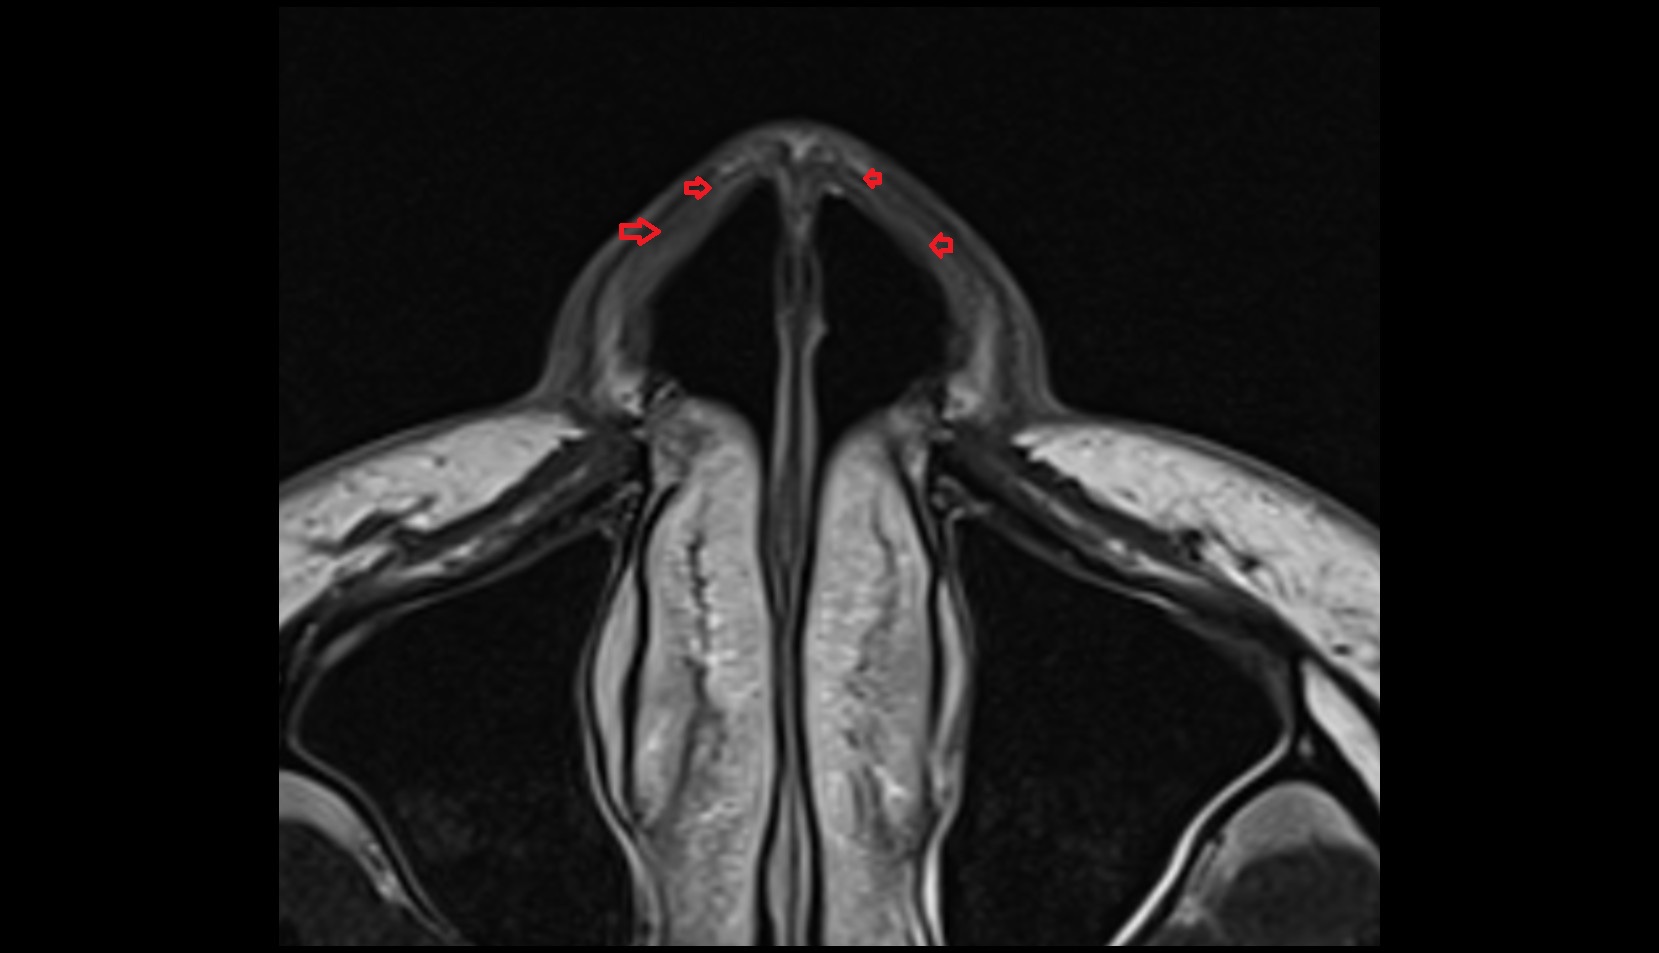

- Corpus cavernosum

- Corpus spongiosum

- Bulb of Penis

- Crus of penis